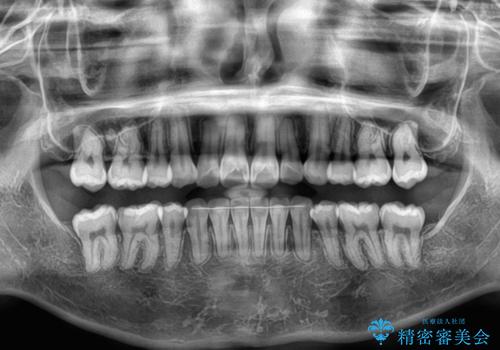

- 上下前歯の叢生を気にして来院された患者様です。

インビザラインでの治療を希望されていて、デコボコの程度が中等度であり、安価なパッケージにて対応可能と判断されたため、インビザライン・モデレートを用いて矯正治療を行うこととしました。

インビザライン・モデレートは、製作できるアライナーの枚数に制限があるため、移動可能な量に限りがあるものの、インビザライン・ライトよりも枚数が多いため、幅広い症例に対応可能です。